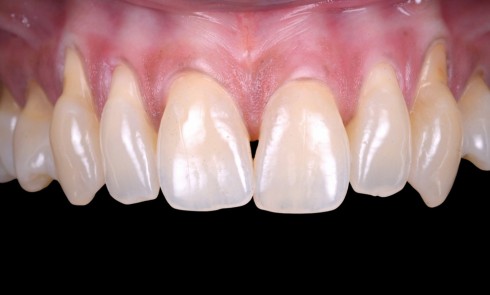

Parodontologie